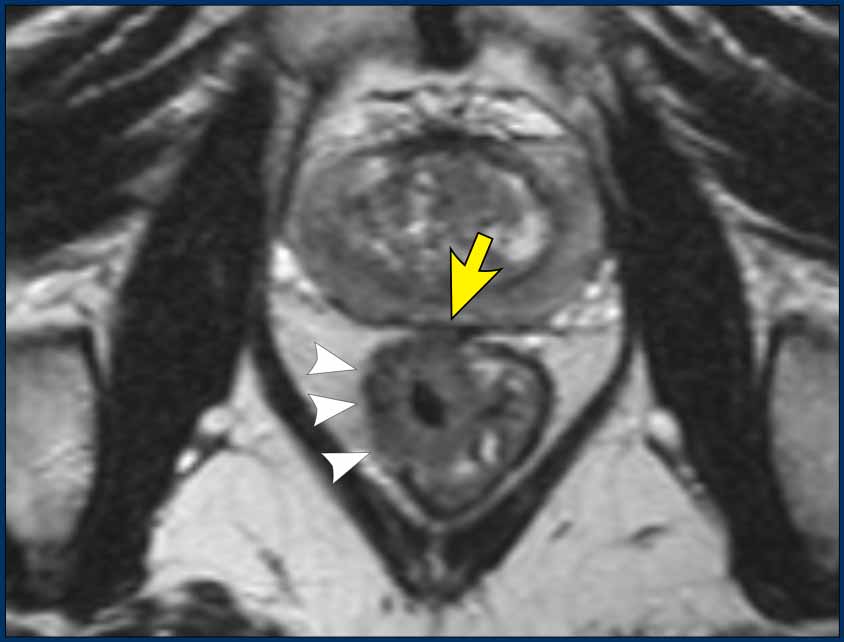

MRI Features

• Often challenging to identify

• Typically presents as long-segment, diffuse bowel wall thickening

• Submucosal growth pattern, yielding a "target" appearance on axial images

• Diffuse mesorectal fat infiltration is common

Images

The provided images demonstrate a signet-ring cell carcinoma with diffuse rectal wall thickening, the classic target appearance, and mesorectal fat infiltration.